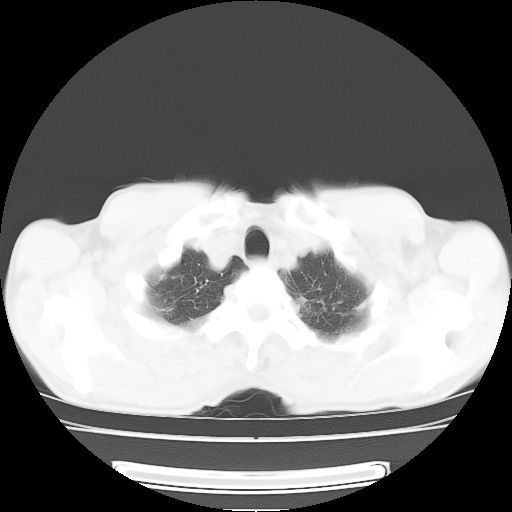

标题: CT25795:感冒后反复咳嗽两月余,痰中带血半月余。X诊断“肺 [打印本页]

标题: CT25795:感冒后反复咳嗽两月余,痰中带血半月余。X诊断“肺

1.双肺肺梗塞(理由:病灶呈三角形,与胸膜相连且局部胸膜肥厚,左心室增大)伴肺感染。

2.一元论双肺感染。

肺梗塞虽然有创意,但不现实。我考虑感染性病灶。

考虑两肺感染性病变,左肺上叶舌段肿瘤性病变待排;建议抗炎治疗后复查。